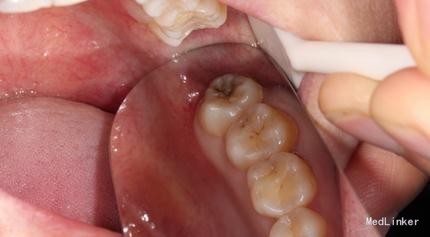

检查: 18.28颌面龋坏,质地软,牙颈部脱矿,叩诊(-),不松动。 37玻璃充填物,叩诊(-),不松动,冷热刺激正常。 38近中水平阻生,牙龈无红肿,叩诊(-),探诊有盲袋,盲袋内食物碎屑。 47缺失多年,48近中向移位,间隙1mm,叩诊(-),不松动。

治疗计划:18、28,38拔除。 37重新充填。 48观察。 治疗:28局麻下拔除。 38阻滞下拔除。